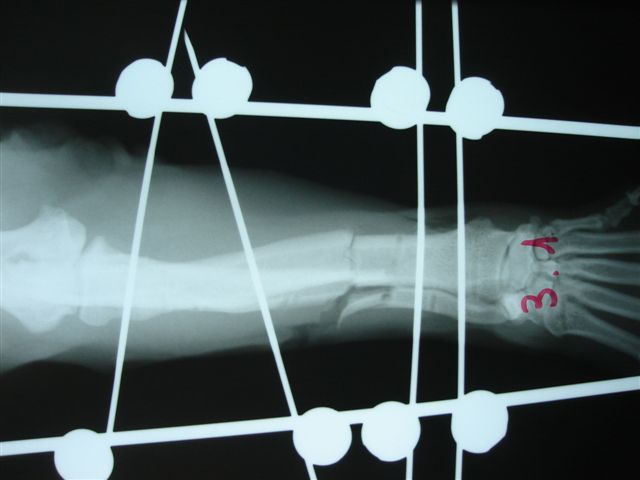

Fijación Externa en IVOT

Fijación Externa

IX CURSO BASICO DE FIJACION EXTERNA.

Casos prácticos alumnos.